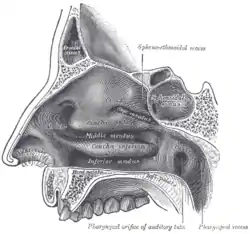

Фронти́т (лат. frontitis), також фронтальний або лобний синусит — вид синуситу, запалення слизової оболонки лобових пазух (sinus frontales).

![]() Місце локалізації фронтиту — sinus frontales Місце локалізації фронтиту — sinus frontales | |